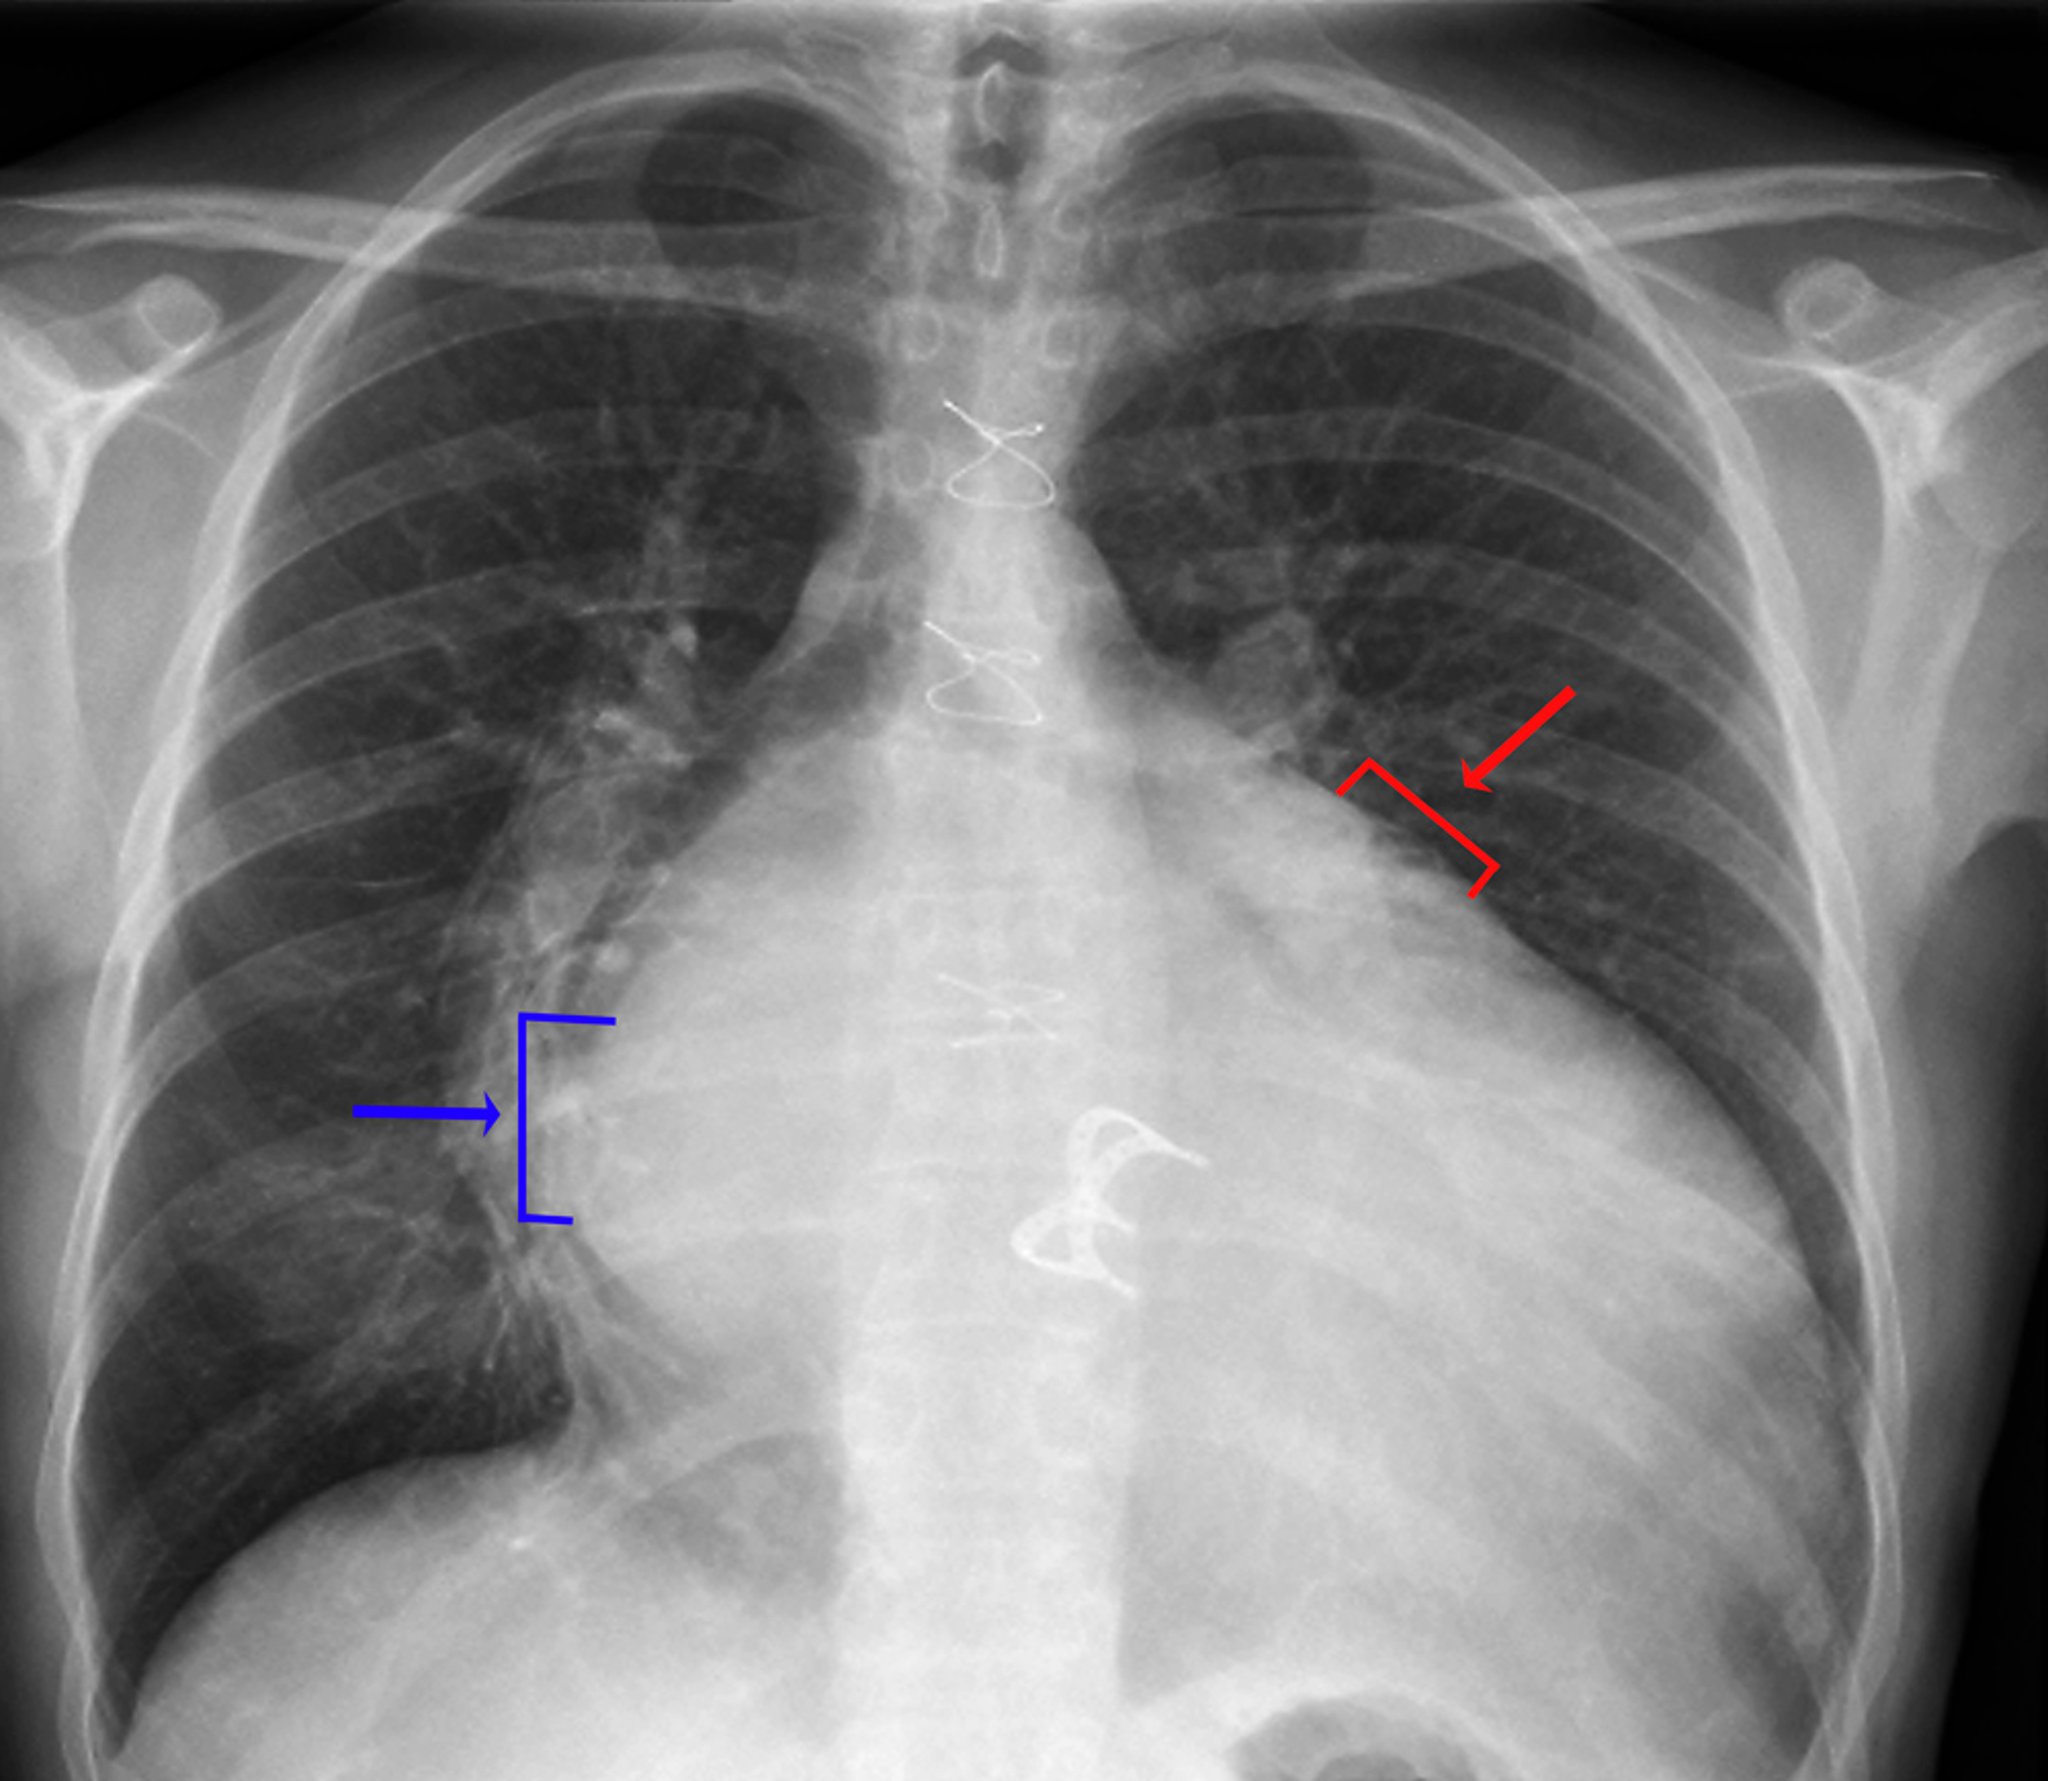

Radiografía de tórax (válvula cardíaca protésica)

Los signos de agrandamiento de la aurícula izquierda incluyen una densidad visible de aurícula izquierda en el hemitórax derecho (flecha azul, signo de doble densidad), mayor distancia (> 7 cm) entre el borde auricular izquierdo en el hemitórax derecho y el bronquio principal izquierdo, un convexidad a lo largo del borde cardíaco superior izquierdo causada por el agrandamiento de la orejuela auricular izquierda (flecha roja) y el ensanchamiento de la carina con mayor separación entre los bronquios principales izquierdo y derecho. Los signos de agrandamiento ventricular izquierdo incluyen un agrandamiento de la silueta cardíaca y el desplazamiento del borde cardíaco izquierdo hacia la izquierda y abajo.